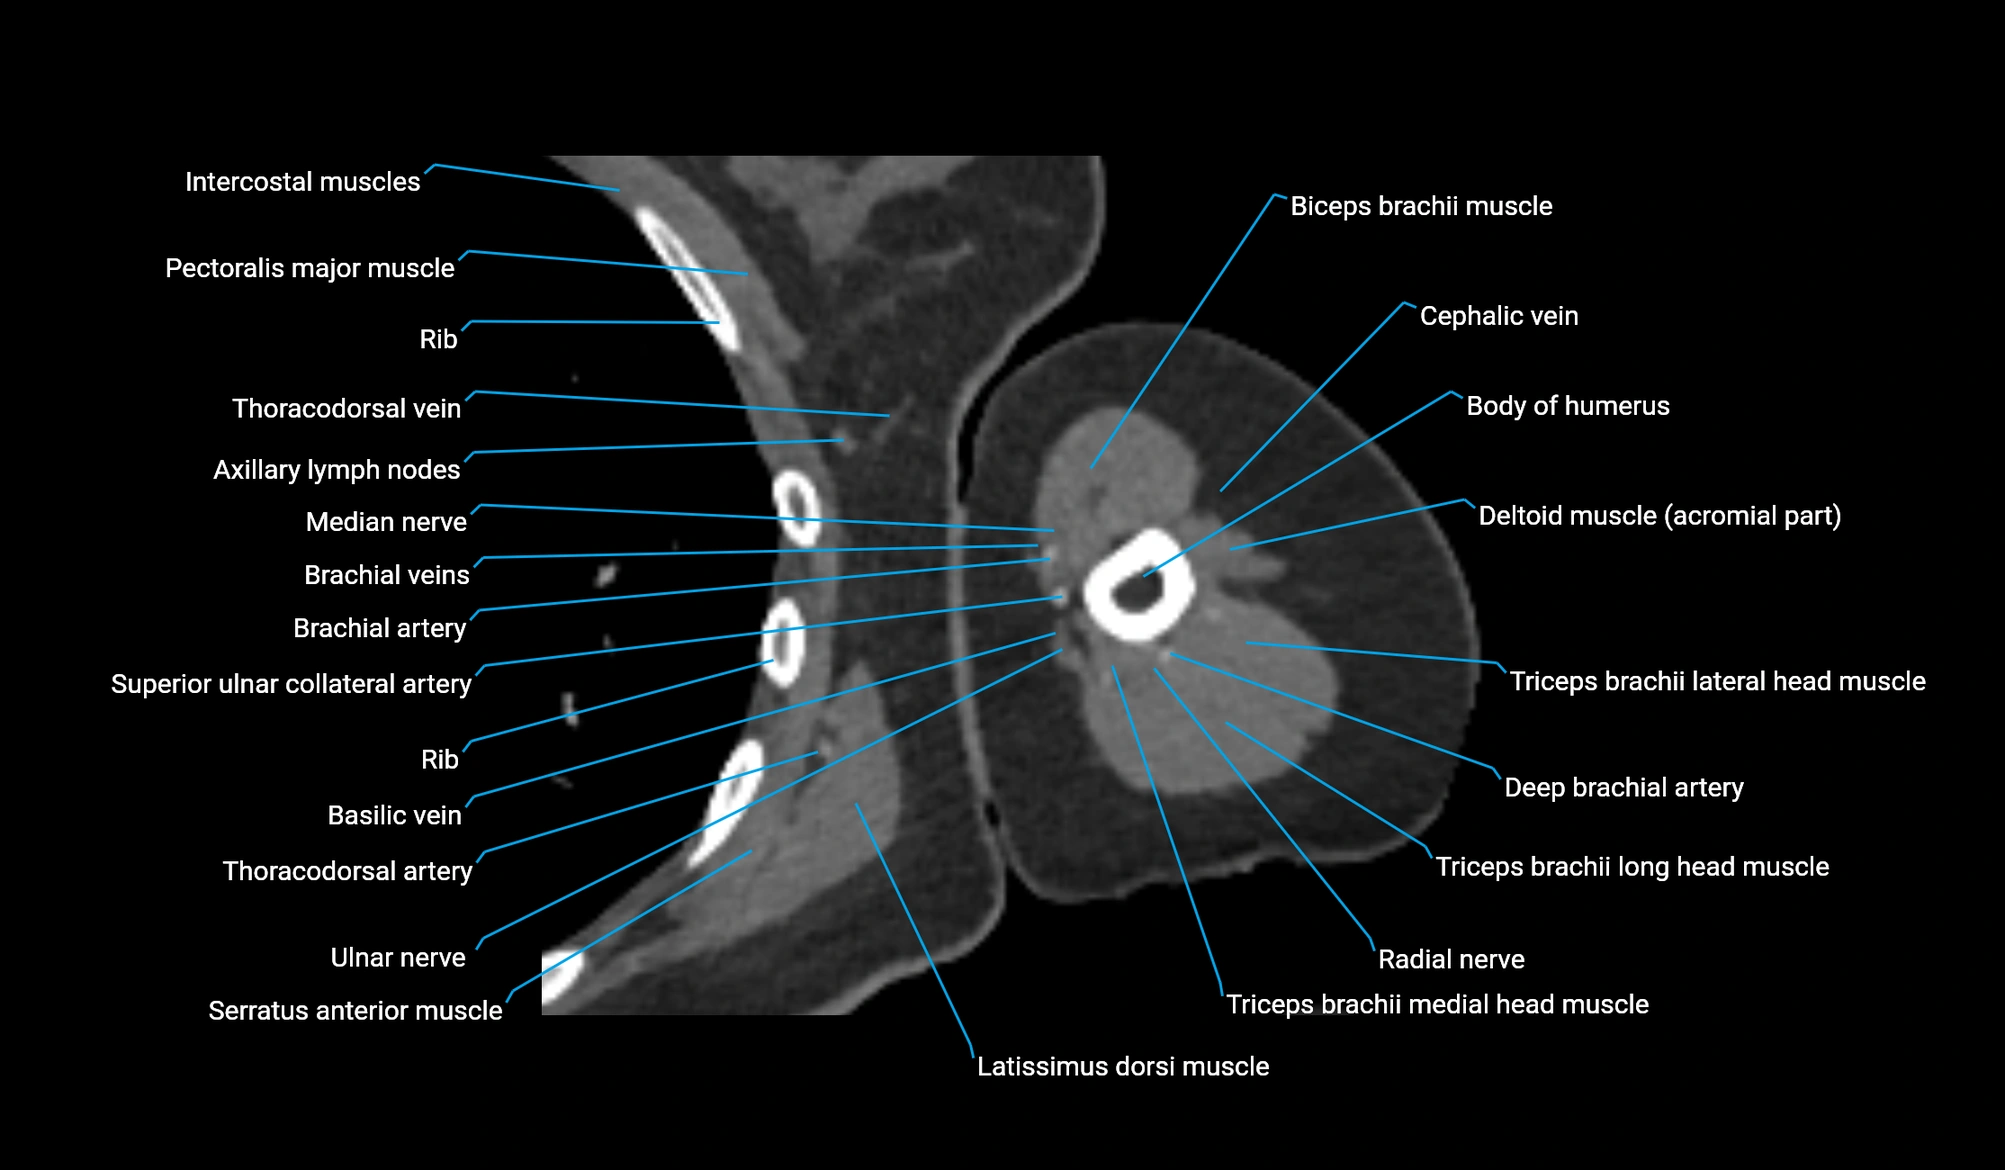

- Body of humerus

- Brachial artery

- Cephalic vein

- Deep brachial artery

- Lateral head of triceps brachii muscle

- Long head of triceps brachii muscle

- Medial head of triceps brachii muscle

- Median nerve

- Pectoralis major muscle

- Radial nerve

- Superior ulnar collateral artery

- Teres major muscle

- Thoracodorsal artery

- Triceps brachii muscle